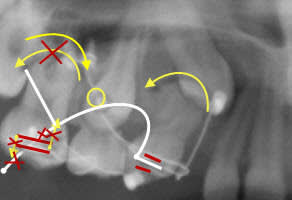

Si on plie simplement la partie distale du fil pour la rendre parallèle au tube molaire, on supprime les composantes aboutissant à la distoversion radiculaire (et mésioversion coronaire).

Et si on augmente cet angle de pliure, on va au contraire entraîner une mésioversion radiculaire (et distoversion coronaire) et on peut supprimer les composantes d'égression prémolaire et d'ingression molaire.

- La courbure du fil faite en distal de la 14 aura une action de distoversion radiculaire.

- La courbure du fil faite en mésial de la 16 aura pour effet d'en limiter les dérives verticales (ingression 16 et égression 14).